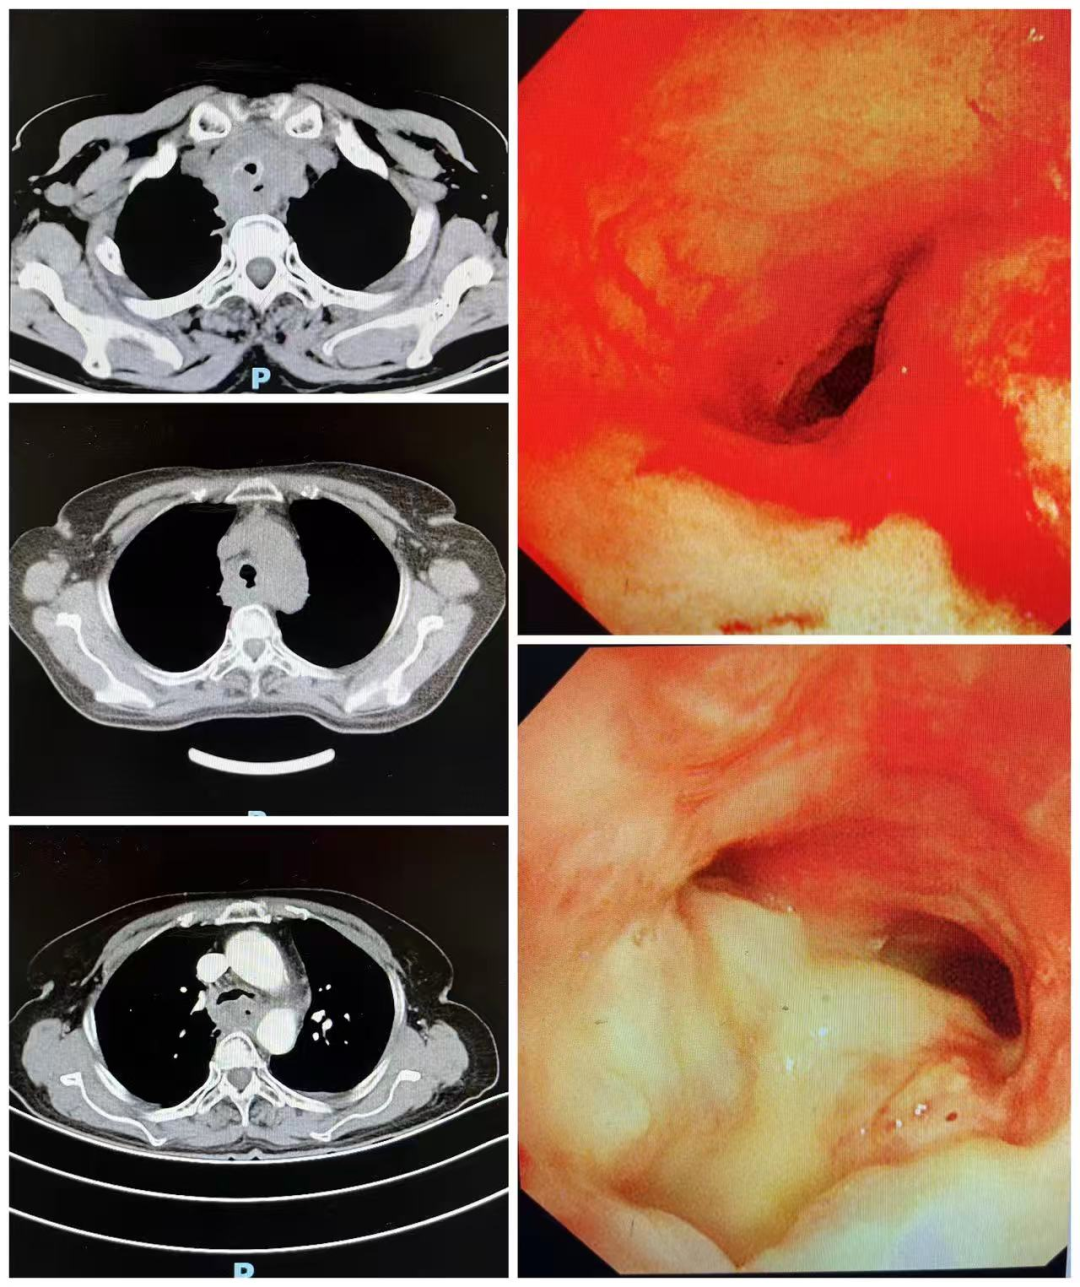

本次接受手术的71岁女性患者,正是面临这样的危急情况。她因“胸闷、喘憋、咳痰一月余,加重伴发热1天”前来就诊。患者既往有食管恶性肿瘤病史,虽曾接受放化疗,但肿瘤仍在恶化,导致呼吸困难入院。进一步检查发现,患者气管严重狭窄,并存在气管食管瘘。由于气道狭窄,患者轻微活动即感憋喘,只能卧床;同时,食物经瘘口误入气管,引发大面积肺炎,痰液难以咳出,存在窒息及生命危险,急需手术干预。

术前胸部CT及气管镜检查提示,患者大气道明显狭窄,狭窄处直径仅约6mm,长度约40mm,远低于正常人15–20mm的气管直径。此外,患者无法耐受缺氧,麻醉风险极高,手术难度大。面对这一复杂病情,肺病二科联合麻醉、医务部、内镜中心及重症医学科等多学科团队,全面评估患者情况,反复讨论并制定了周密的手术方案,全力保障患者安全。

患者术后胸部CT及镜下图片